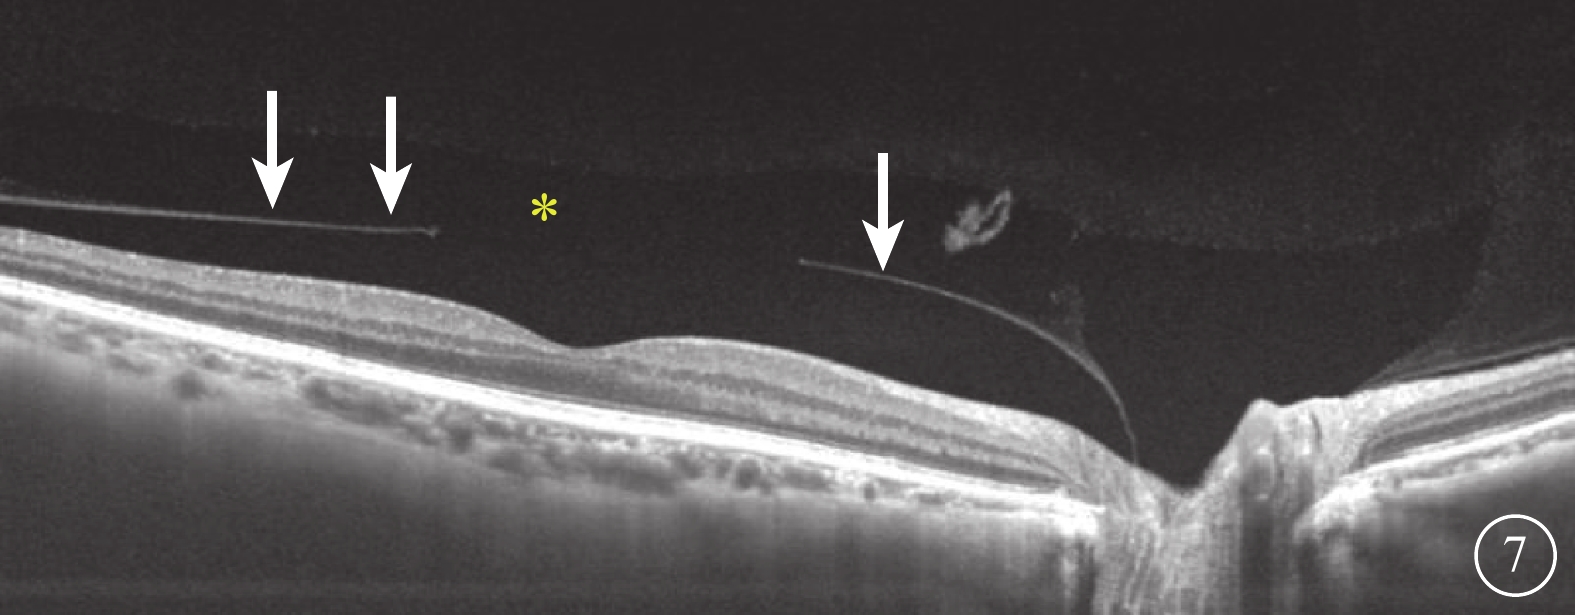

SS-OCT檢查結果顯示,所有受檢眼均在同一掃描層面觀察到PPVP與Martegiani區(圖6),其中PPVP與Martegiani區存在連接通道54只眼(77.0%)。其形態特點與SD-OCT檢查所見相似,但PPVP成像更清晰,與Martegiani區的連接通道更清楚(圖6)。PPVP前存在黃斑上囊7只眼。PPVP伴PVD 4只眼,其中玻璃體后皮質破裂后界不完整(圖7)2只眼。同時行SD-OCT及SS-OCT檢查的24只眼中,SD-OCT、SS-OCT檢查發現PPVP與Martegiani區連接通道分別為18、21只眼;SD-OCT檢查未發現黃斑上囊2只眼,但SS-OCT檢查發現存在。

圖7

受檢眼SS-OCT像。可見明顯PVD(白箭)伴PPVP(黃色星);PPVP后界破裂,與PVD產生出現連接通道

圖7

受檢眼SS-OCT像。可見明顯PVD(白箭)伴PPVP(黃色星);PPVP后界破裂,與PVD產生出現連接通道

SS-OCT檢查結果顯示,所有受檢眼均在同一掃描層面觀察到PPVP與Martegiani區(圖6),其中PPVP與Martegiani區存在連接通道54只眼(77.0%)。其形態特點與SD-OCT檢查所見相似,但PPVP成像更清晰,與Martegiani區的連接通道更清楚(圖6)。PPVP前存在黃斑上囊7只眼。PPVP伴PVD 4只眼,其中玻璃體后皮質破裂后界不完整(圖7)2只眼。同時行SD-OCT及SS-OCT檢查的24只眼中,SD-OCT、SS-OCT檢查發現PPVP與Martegiani區連接通道分別為18、21只眼;SD-OCT檢查未發現黃斑上囊2只眼,但SS-OCT檢查發現存在。

圖7

受檢眼SS-OCT像。可見明顯PVD(白箭)伴PPVP(黃色星);PPVP后界破裂,與PVD產生出現連接通道

圖7

受檢眼SS-OCT像。可見明顯PVD(白箭)伴PPVP(黃色星);PPVP后界破裂,與PVD產生出現連接通道